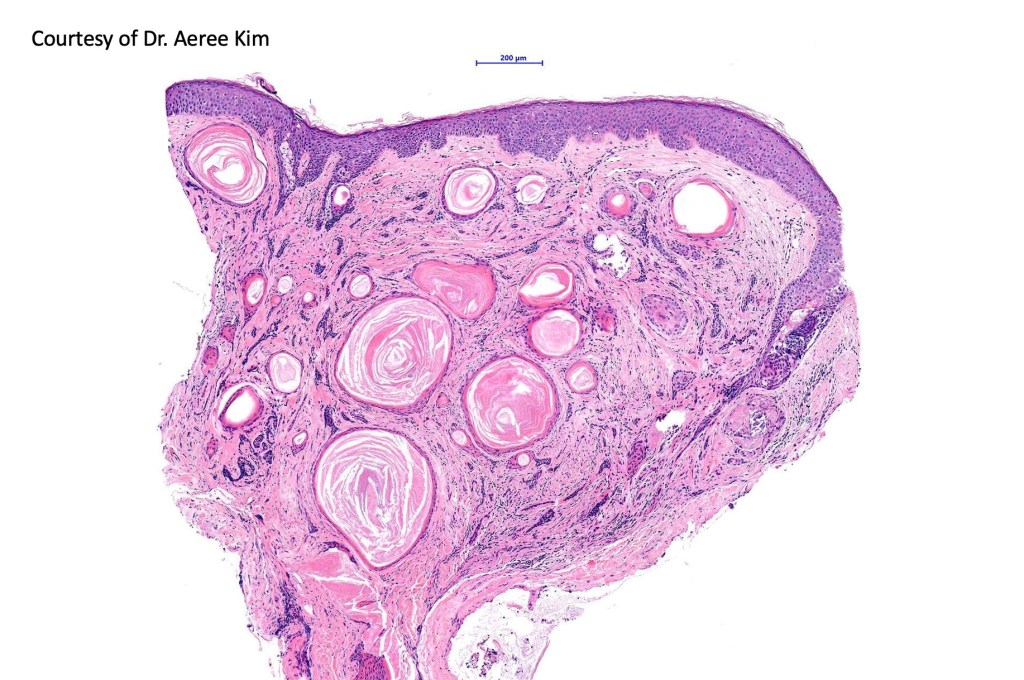

Histological features

•Consists of narrow epithelial strands & keratocysts embedded in a dense stroma

•Generally involves superficial & mid dermis but does not extend into the subcutaneous fat

•No evidence of glandular differentiation

•Calcification, foreign body giant cell reaction to keratin & bone are inconstant findings

•Epithelial stands may arise from follicular epithelium